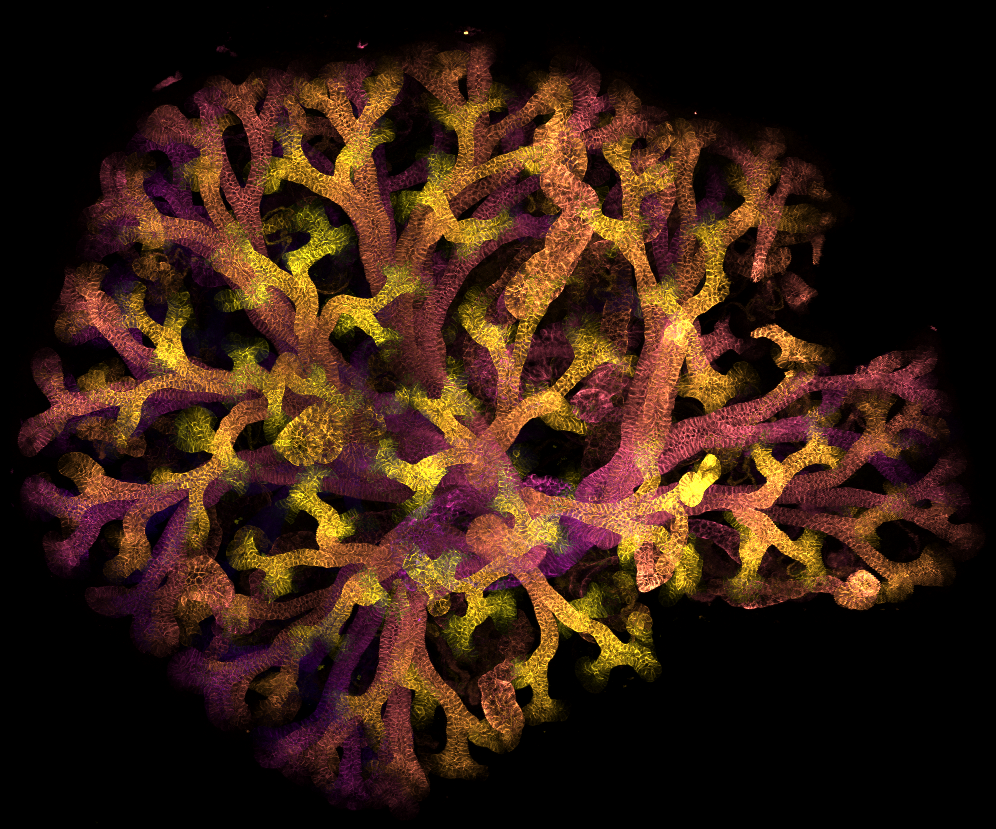

Fluorescent microscopic image showing a branching, tree‑like structure in shades of yellow, orange and purple against a black background

A forest built for filtration – entered by Emily Moore, PhD Student This image shows branching tubes in a developing mouse kidney. These collecting ducts form like a tree, growing outward from a central point to collect and carry waste to the bladder. The pattern mirrors kidney development in humans, helping scientists understand how healthy kidneys form and how this process can be disrupted by disease.